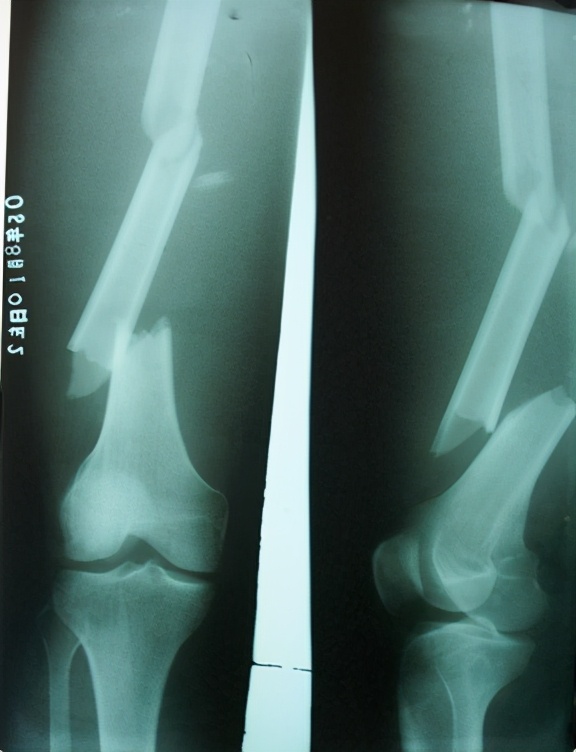

这张图,受过伤的人一定都见过,这是大腿中部,也就是股骨中段的骨折。

当我们遇到交通事故的时候,其中汽车撞人,导致大腿骨折,尤其是大腿中部的骨折( 股骨 中段骨折),是很常见的伤情,无论是车主还是伤者,都关心一件事,伤者发生大腿中部的 股骨 中段骨折怎么索赔,这个伤情一般分为几种情况赔偿,这次给大家介绍诊断为“股骨”中部/中段,且单纯的骨折的相关赔偿项目,这个也是可以预期,比如,